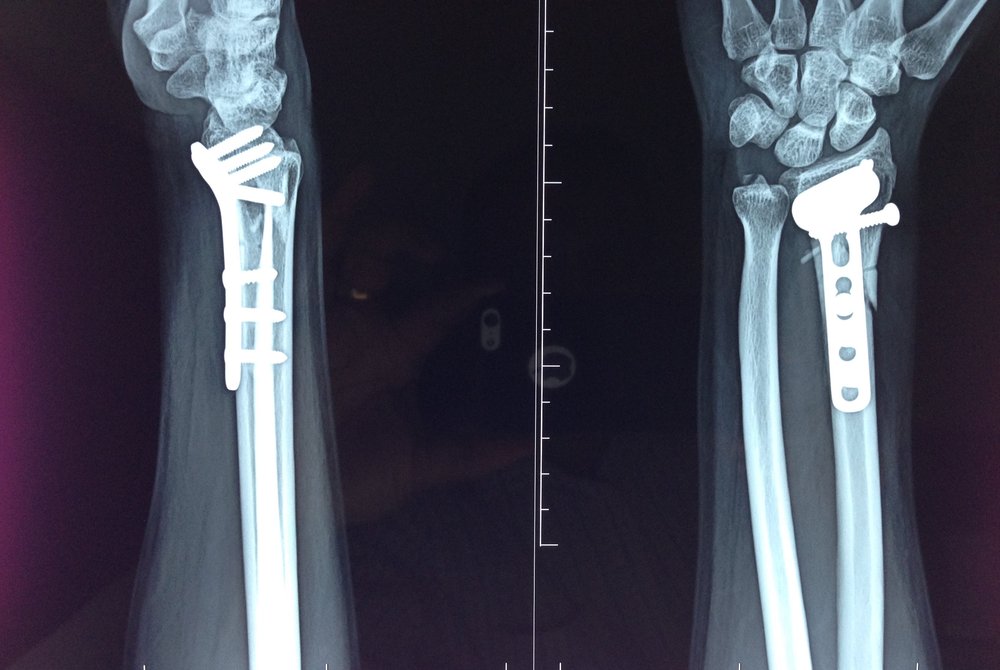

Χειρουργική Θεραπεία

Όταν το κάταγμα εμφανίζει μεγάλη συντριβή (πολλά μικρά οστικά τεμάχια) ή όταν είναι ασταθές και δεν μπορεί να συγκρατηθεί με τον γύψο, τότε απαιτείται χειρουργική θεραπεία.

Αυτή ονομάζεται ανοικτή ανάταξη και εσωτερική οστεοσύνθεση.

Ανάλογα με το κάταγμα, υπάρχουν μια σειρά από επιλογές για τη συγκράτηση του οστού στη σωστή θέση.

- Πλάκα με βίδες (από τιτάνιο ή ανοξείδοτο χάλυβα)